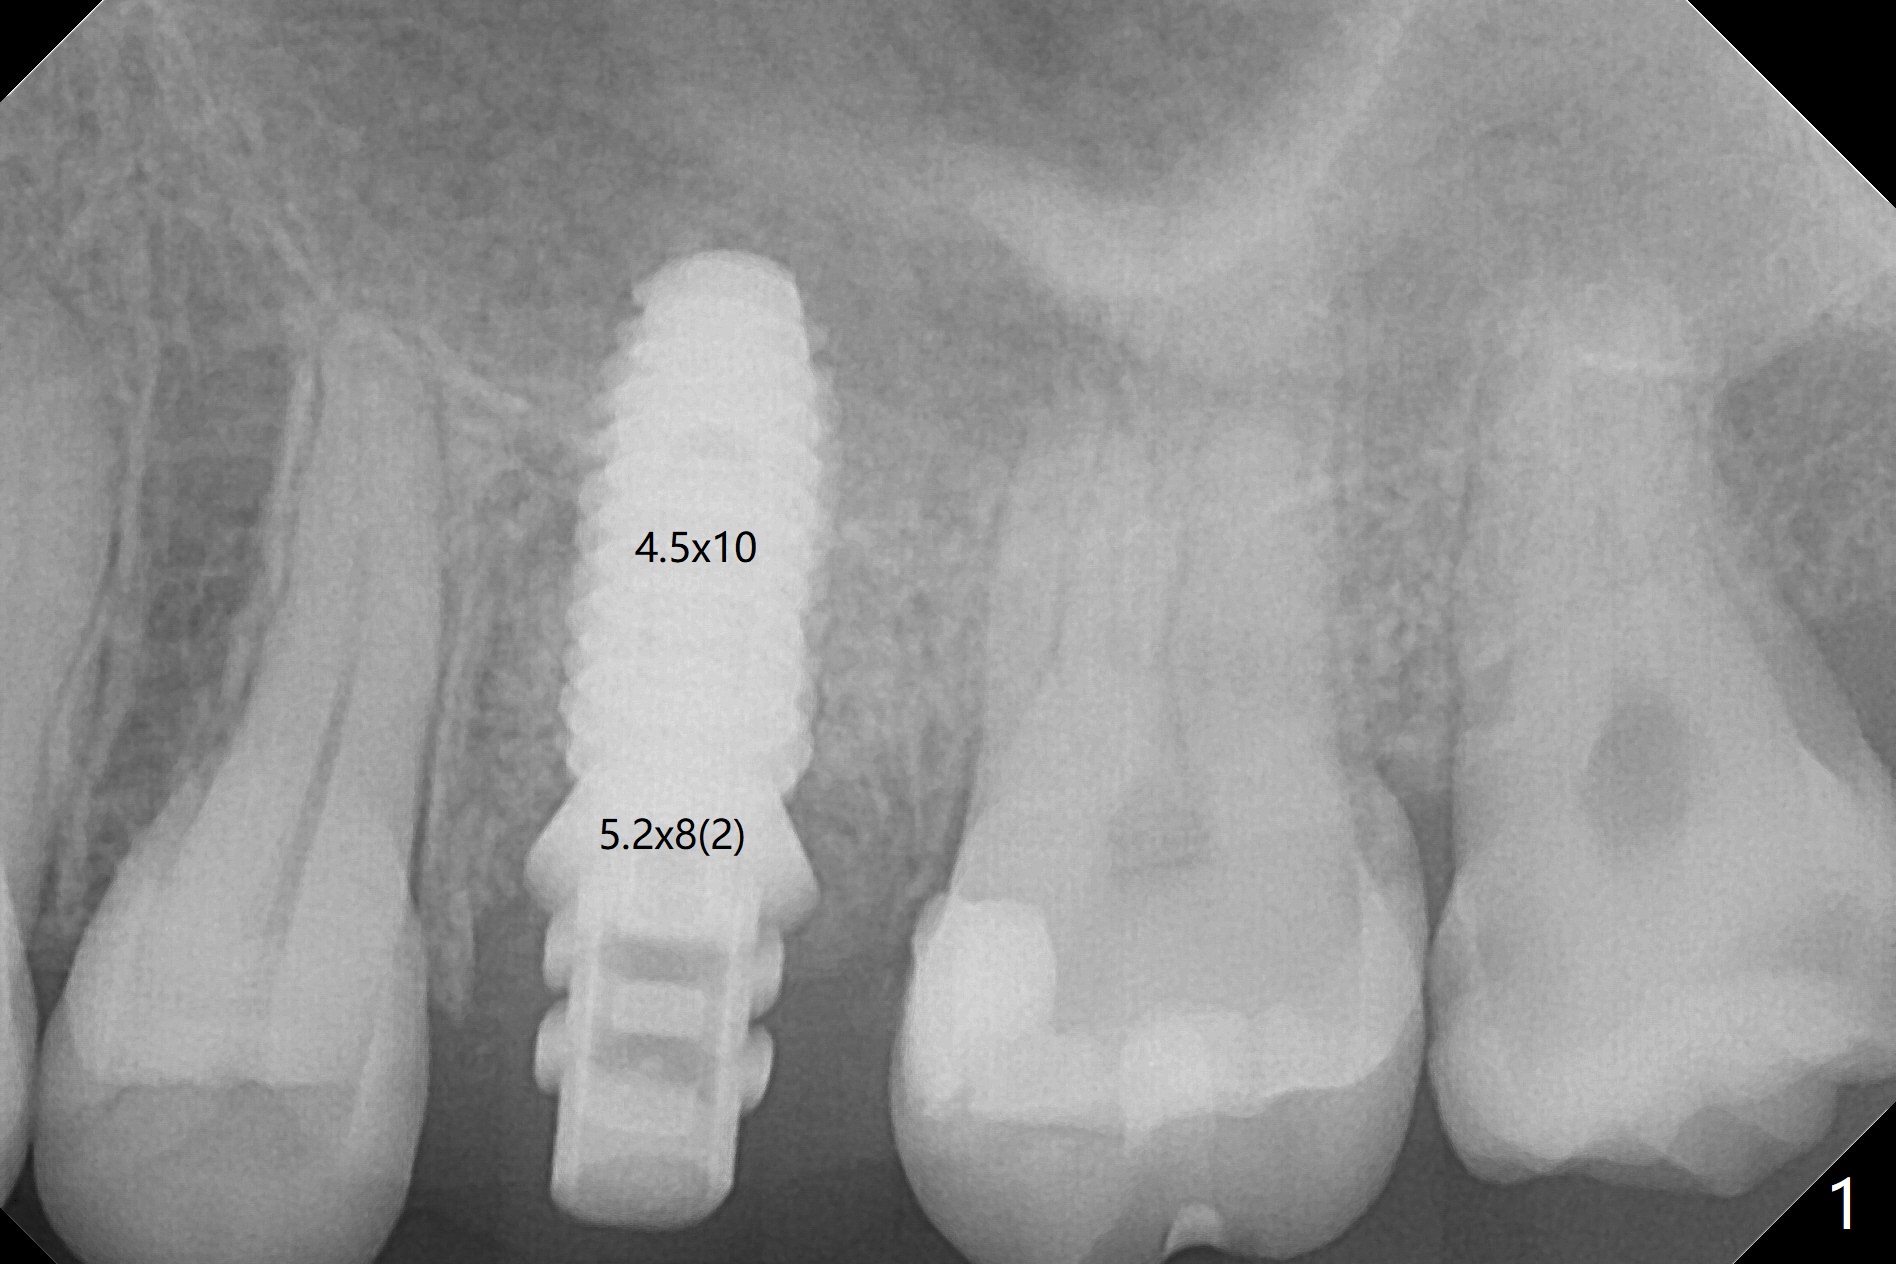

When a 4.5x10 mm implant is placed with sinus lift at #14 (Fig.1), a 5.2x8(2) mm temporary abutment is inserted with height adjustment. Advantage is that an immediate provisional (Fig.2 yellow lines; Fig.3 P) has an ideal emergency profile so that there is less chance of food impaction associated with the future permanent crown. It appears that the mesial portion of bone graft in the mesial gap has been converted to the native bone (lamellar) in 3 months (Fig.4). Bone graft appears to be integrated to the native bone and the implant 14 months postop (Fig.5).